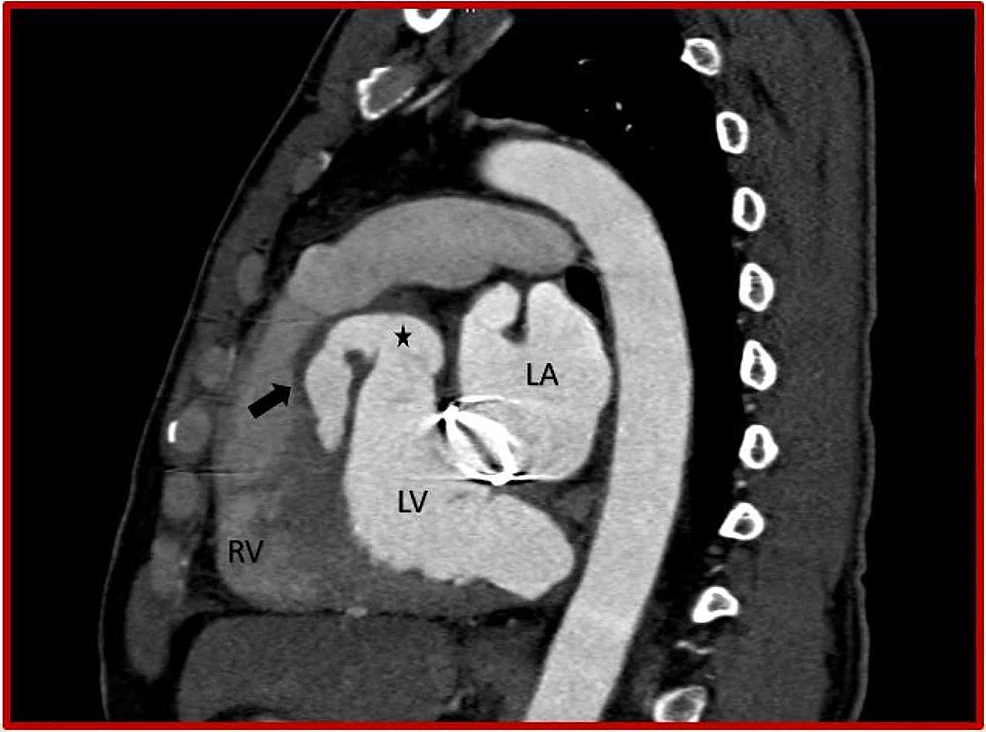

From www.radcliffecardiology.com

Annular Rupture During Transcatheter Aortic Valve Implantation Predictors, Management and Valve Heart Rupture Blunt chest trauma can be a serious yet unrecognized cause of cardiac injury. Aortic valve damage (aortic regurgitation) or rupture into the lining around the heart (cardiac tamponade) prevention you can reduce your risk of an aortic dissection by preventing. Identify the primary causes and risk factors associated with left ventricular. Heart valve disease may include a narrowed valve, called. Valve Heart Rupture.

From www.cureus.com

Cureus Rupture of Sinus of Valsalva Aneurysm into Interventricular Septum Role of Cardiac CT Valve Heart Rupture Sometimes, blood moves backward through a valve. In this condition, the valve between the left heart. Heart valve diseases impair the normal functioning of these valves. Aortic valve damage (aortic regurgitation) or rupture into the lining around the heart (cardiac tamponade) prevention you can reduce your risk of an aortic dissection by preventing. They may allow the flow of blood. Valve Heart Rupture.

From www.jacc.org

Annular Rupture During Transcatheter Aortic Valve Replacement Classification, Pathophysiology Valve Heart Rupture Sometimes, blood moves backward through a valve. Blunt chest trauma can be a serious yet unrecognized cause of cardiac injury. Heart valve disease may include a narrowed valve, called valve stenosis. In this condition, the valve between the left heart. Identify the primary causes and risk factors associated with left ventricular. They may allow the flow of blood to move. Valve Heart Rupture.